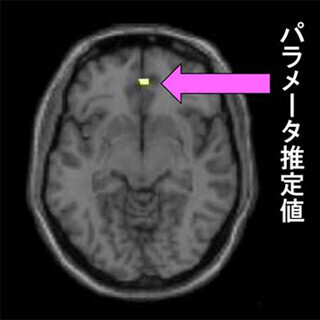

今回の研究はASD特徴がある人物の行動パターン記述分(ASD文)と、定型発達(Typically developing:TD)の人物の行動パターン記述文(TD文)をASDの成人15名(平均26.7歳)と、年齢・知能指数を合わせたTDの成人15名(平均26.1歳)に読んでもらい、自分にも当てはまるか、主語となる人物が自分に似ているかを判断してもらい、その際の脳活動を調べるというもの。この結果、ASDの成人はASD特徴がある人物を判断する際に、自己の処理、共感に関わる腹内側前頭前野が有意に活動していることが確認され、自身と類似したASD人物に対して共感的な反応を示していることが判明した。

また、ASD人物を判断する場合、自閉症スペクトラム指数の得点が高いほど、腹内側前頭前野の活動が高くなることも確認され、ASDの傾向が高い人ほど、ASD人物に対して共感的に理解している可能性が示唆されたという。